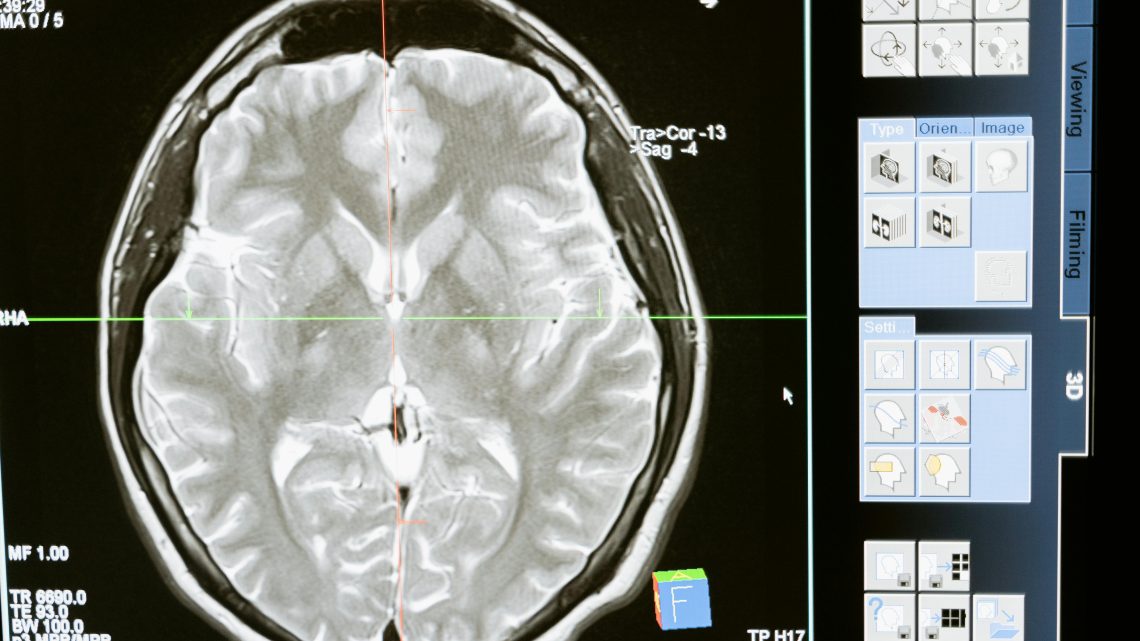

Со временем формируется атеросклеротическая бляшка, которая уменьшает просвет артерии. Это приводит к снижению перфузии органов и тканей. Если речь идет о сонных артериях, страдает головной мозг. При поражении коронарных сосудов – миокард. Если вовлечены артерии нижних конечностей, развивается хроническая ишемия ног.

Назначаются препараты при атеросклерозе сонных артерий, направленные на снижение риска ишемического инсульта. Это необходимо, если поражены эти сосуды шеи. При церебральной форме применяются препараты от атеросклероза головного мозга, улучшающие реологические свойства крови и мозговую перфузию.